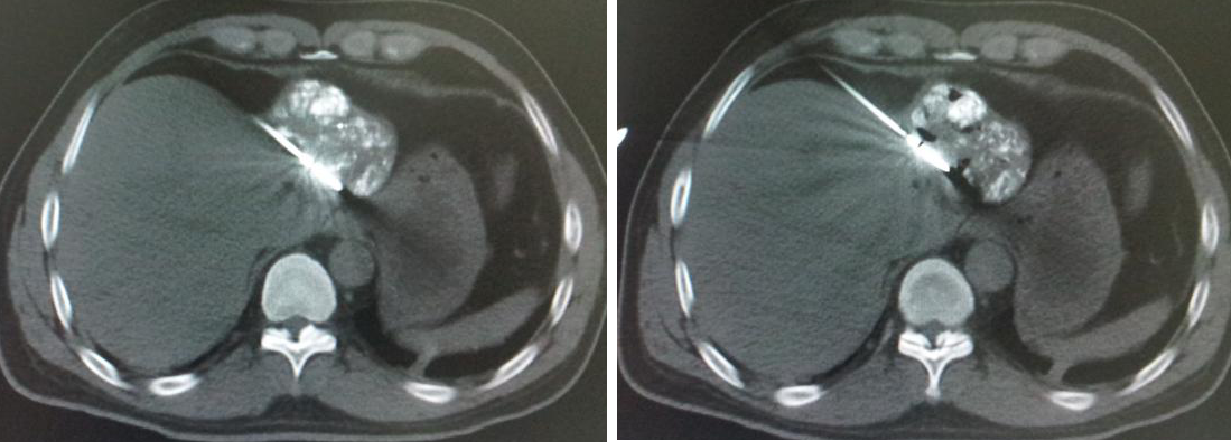

2011-01-06我院上腹部CT:

肝左叶巨块型肝癌(13.8cm×9.1cm),伴肝右后叶子灶,门静脉左支、肝左静脉及下腔静脉内癌栓。

2011-01-07 对肝左叶病灶行第1次TACE术(碘化油18ml,THP 46mg)

2011-02-12复查CT示:肝左叶碘油散在沉积,病灶大部分仍有活性,肝右后叶病灶未见碘油沉积;门静脉癌栓较前进展,累及主干及右支;肝左静脉及下腔静脉内癌栓无明显变化。AFP:26802 ng/ml。

2011-02-16行第2次TACE术(碘化油15ml,THP 45mg)

2011-06-14行第3次TACE术(碘化油15ml,THP 35mg)

2011-08-15复查CT示:肝左叶病灶大小较前相仿,仍有肿瘤残留。